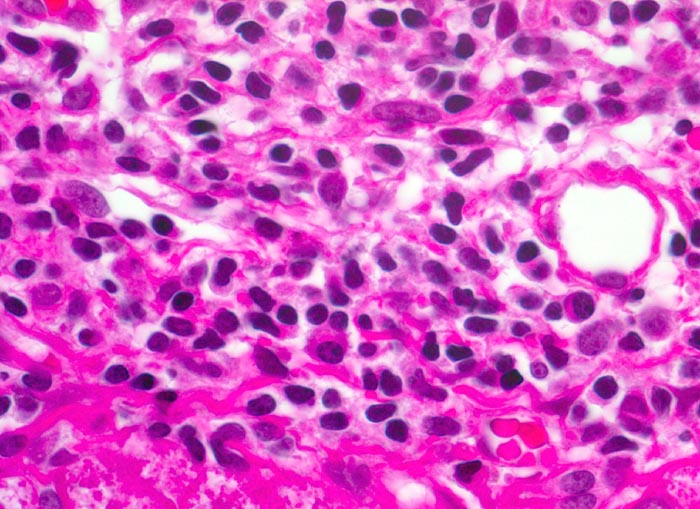

Morphologische Merkmale:

• Dichte mononukleäre portale und lobuläre Entzündungsinfiltrate mit Ausbildung von Lymphfollikeln in den Portalfeldern.

• Übergreifen der Entzündung auf das Parenchym (=Interface oder Grenzzonenhepatitis).

• Abgerundete hypereosinophile apoptotische Hepatozyten (Councilman-Körperchen).

• Geringe Portalfeldfibrose. Das sollte der Kliniker dem Pathologen mitteilen: